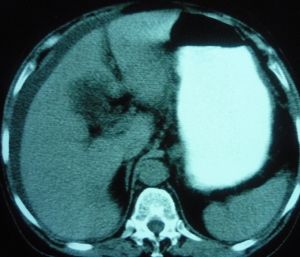

5、CT掃描:鑑別腎囊腫與腫瘤,CT是最精確的。囊液密度近似於水,而腫瘤的密度則與正常腎實質相近。靜脈注射造影劑後,腎實質變得更為濃密,而囊腫仍不受影響;囊腫壁與腎實質有明顯界限,而腫瘤則無;囊腫壁很薄,腫瘤卻不然。從許多方面來說,鑑別囊腫和腫瘤CT要優於穿刺抽液判斷。